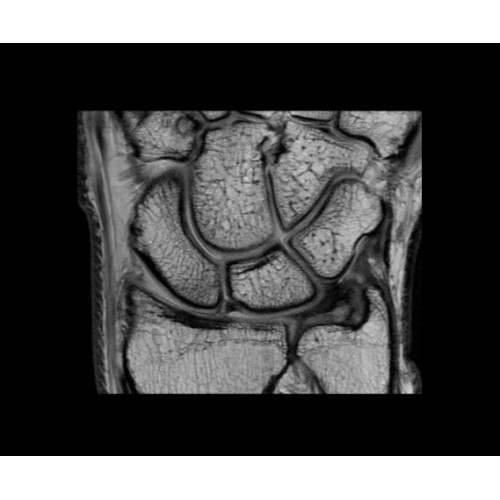

Кроме того, в результате использования технологии TOF и инновационной технологии реконструкции Q.Clear вы сможете добиться прекрасного соотношения сигнал/шум. А благодаря технологии нулевого времени эхо (ZTE) визуализировать костную структуру без ионизирующего излучения. Все эти разработки для улучшения качества сканирования и точности анализа помогут вам использовать весь потенциал ПЭТ/МРТ.

• МРТ с функцией нулевого времени эхо (ZTE) отличается точностью, возможностью персональных настроек и отсутствием ионизирующего излучения. Она приходит на смену традиционному исследованию на основе рентгеновского излучения. МРТ с функцией нулевого времени эхо (ZTE) на базе SIGNA ПЭТ/МРТ является более надежной и быстрой по сравнению с системами, использующими сверхмалое время эхо (UTE).